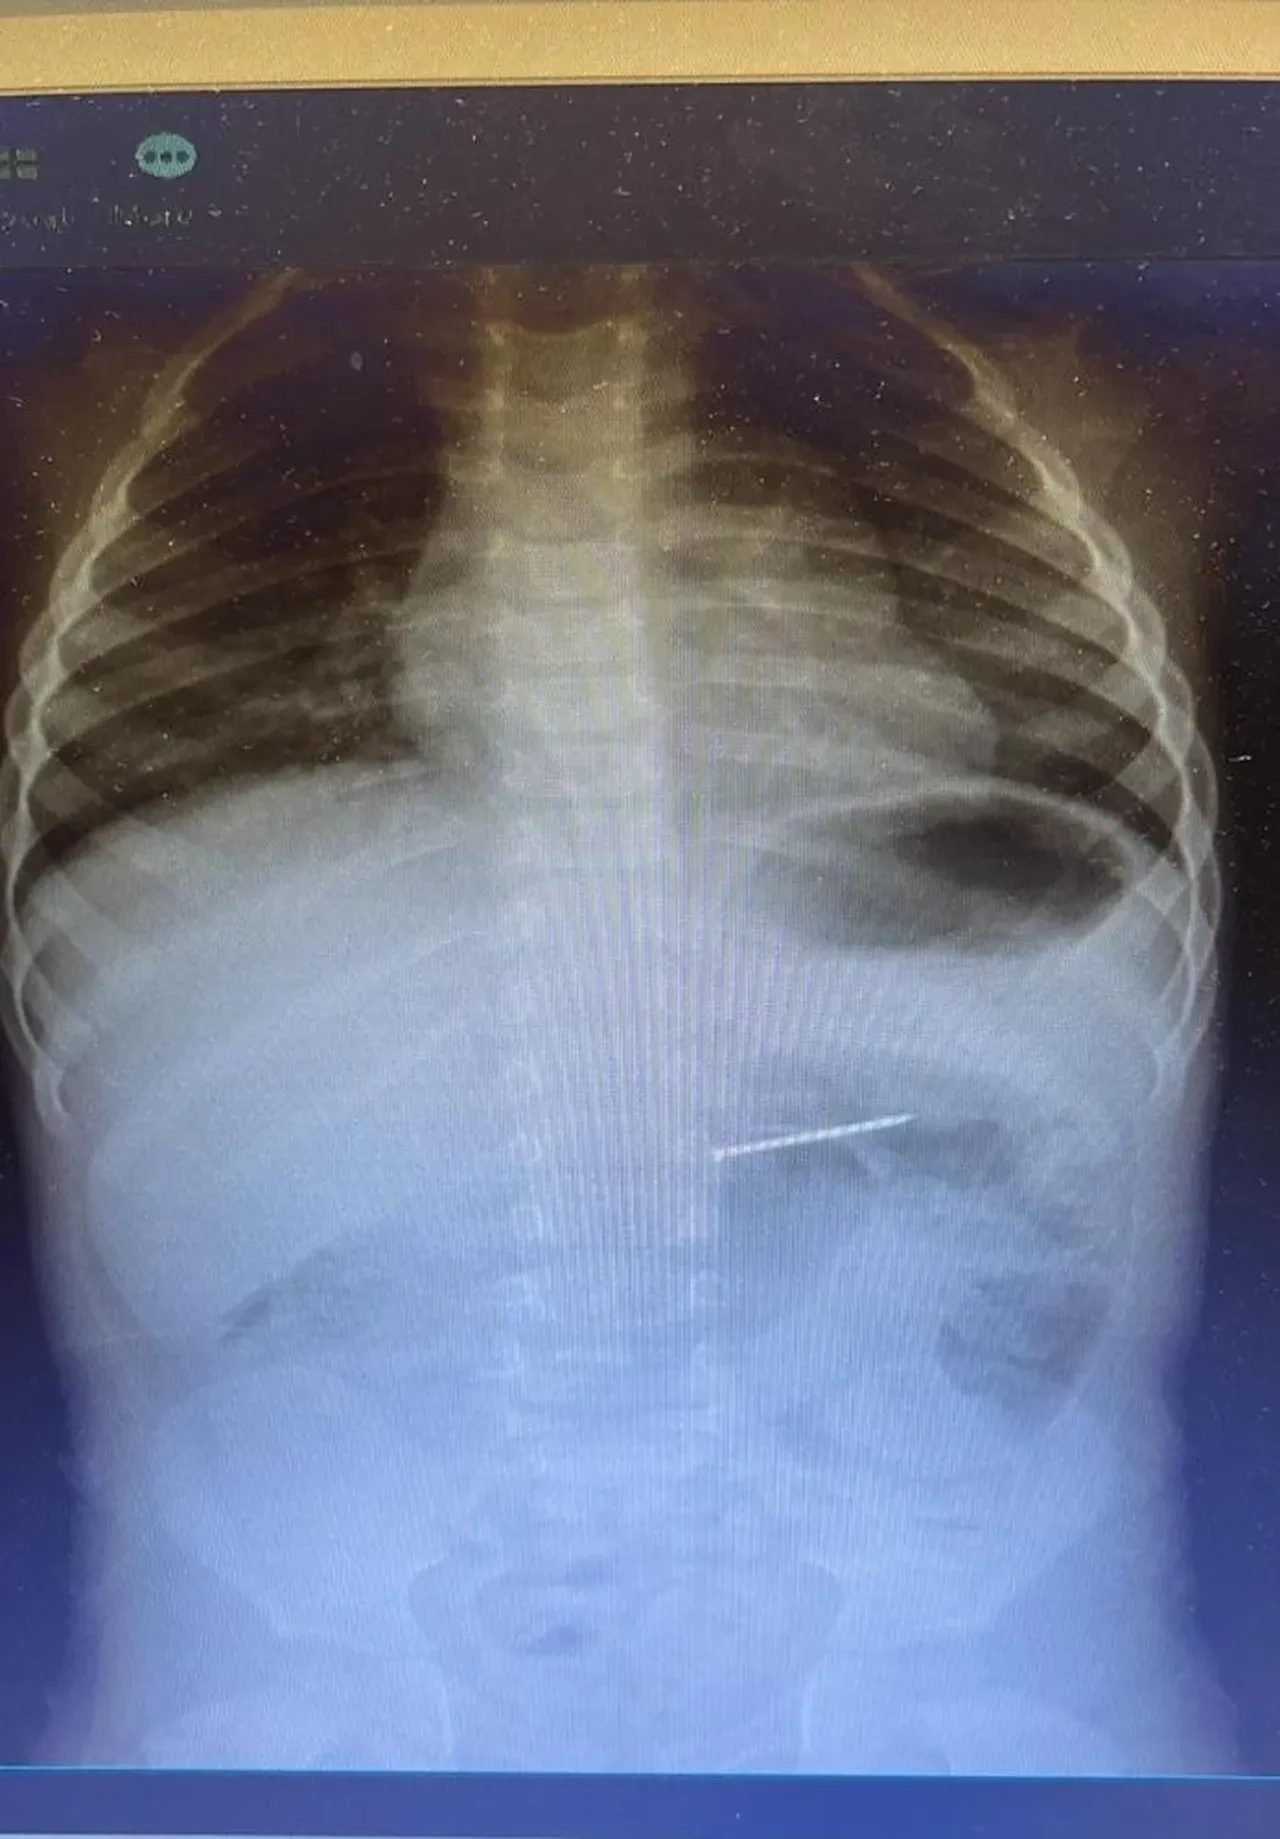

Radyolojik inceleme sonucu yaklaşık 4 santimetre uzunluğundaki çivinin midedeki konumu tespit edildi ve hemen endoskopik müdahale yapıldı. Yapılan işlemle çivi, herhangi bir komplikasyona yol açmadan başarılı şekilde çıkarıldı. Hasta, kısa süreli gözlem amacıyla serviste takip altına alındı ve sağlık durumu stabil şekilde taburcu edildi.